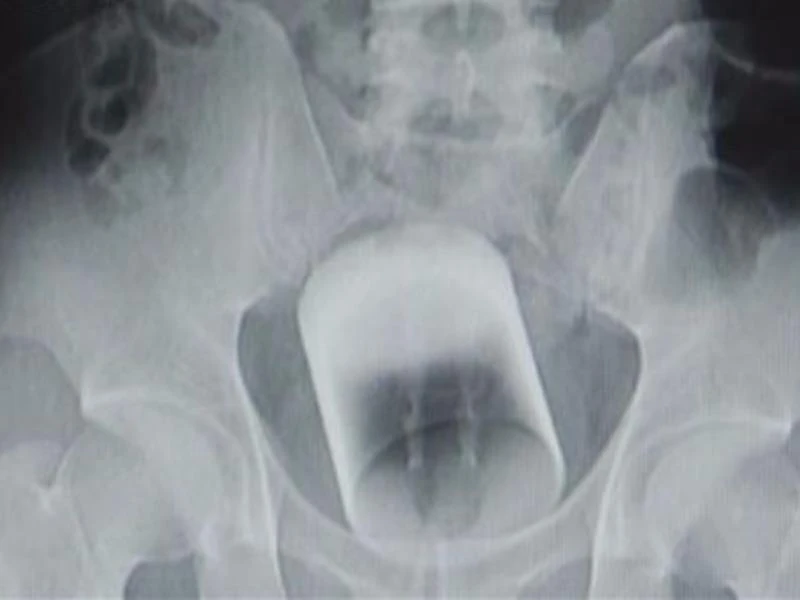

Phim chụp X-Quang cho thấy một chiếc cốc nằm trong hố chậu bệnh nhân. Ảnh: Kankanews

Shanghaiist cho biết, Anh ta đã chạy đến bệnh viện vào lúc 2 giờ sáng, la hét nhờ giúp đỡ. Các bác sĩ nhanh chóng chụp X- quang và phát hiện ra nguyên nhân. Đó là một chiếc cốc thủy tinh, cao 8 cm và có đường kính 7 cm, nằm phía trên trực tràng của bệnh nhân. Bác sĩ nói rằng, chiếc cốc có thể lấy mạng anh ta bất cứ lúc nào nếu nó không được nhanh chóng lấy ra.